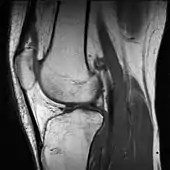

In addition, variants of false color such as pseudocolor, density slicing, and choropleths are used for information visualization of either data gathered by a single grayscale channel or data not depicting parts of the electromagnetic spectrum (e.g. elevation in relief maps or tissue types in magnetic resonance imaging).

A pseudocolor image (sometimes styled pseudo-color or pseudo color) is derived from a grayscale image by mapping each intensity value to a color according to a table or function.[7] Pseudo color is typically used when a single channel of data is available (e.g. temperature, elevation, soil composition, tissue type, and so on), in contrast to false color which is commonly used to display three channels of data.[4]

Depending on the table or function used and the choice of data sources, pseudocoloring may increase the information contents of the original image, for example adding geographic information, combining information obtained from infrared or ultra-violet light, or other sources like MRI scans.[9]